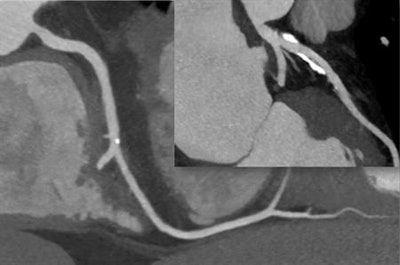

CT scan shows two separate coronary arteries without stenosis or narrowing. There is calcification, and if CT is not performed well (high motion, low-quality image), these calcifications can cause false-positive findings. Image courtesy of Dr. Stephan Achenbach."CT is particularly good at identifying those patients without stenosis who do not require further work-up. Effectively, showing that the coronary arteries are normal is the main value of CT," he said.